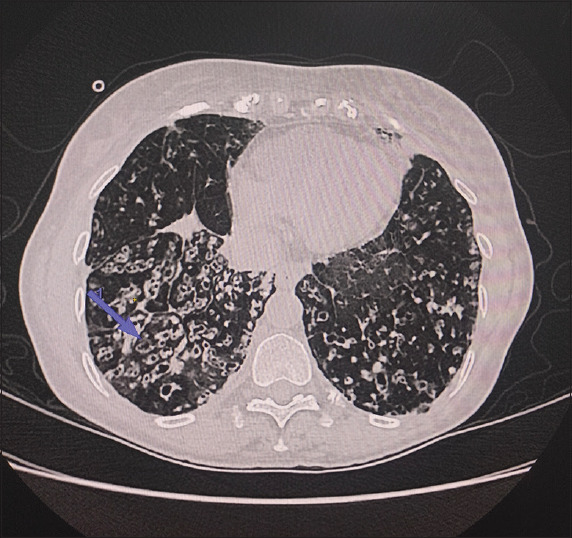

Pulmonary talaromycosis in a non-HIV individual-A rare case report from Southern India.